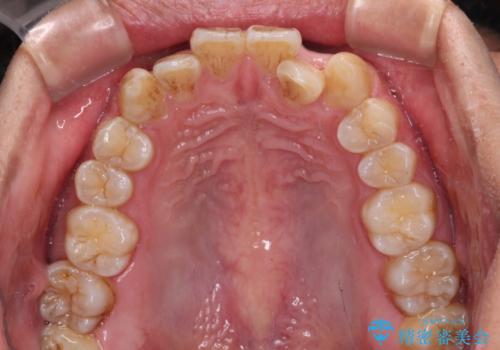

- 前歯のデコボコを気にして来院された患者様です。

極力費用を抑えた上で、自己管理の煩わしの少ない装置を希望とのことで、メタルブラケットによるワイヤー矯正を選択されました。

舌の突出癖があり、デコボコが解消される際に出っ歯傾向になる恐れがあるため、舌のトレーニングを行っていただきながら、矯正治療を進めていくこととしました。